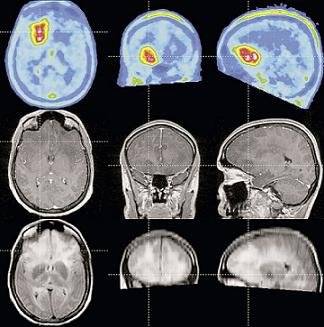

Utilizaron sistemas de scanner cerebral para monitorear los patrones cerebrales y notaron que, al momento de quebrar una promesa, se registra un mayor nivel de actividad en las regiones relacionadas al procesamiento de la emoción y el control. Al observar estos resultados, concluyeron que romper la palabra podría generar un conflicto emocional ya que se suprime la respuesta honesta.

Yendo aún más lejos, aseguran que ciertos patrones cerebrales podrían servir para predecir que una persona va a mentir. Dicho en otras palabras: al momento de hacer una promesa, tanto los mentirosos como los honestos juran que van a cumplir. Sin embargo, la actividad de su cerebro es marcadamente diferente, según afirman los investigadores de Suiza.